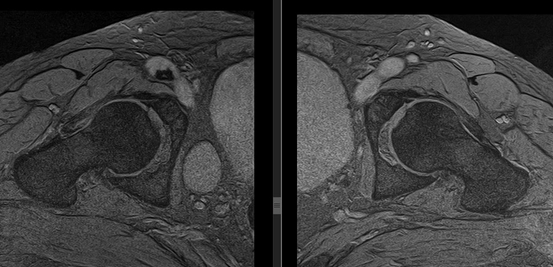

Рисунок 3. МРТ тазобедренных суставов в косо-аксиальной плоскости.

Суставной хрящ головки бедренной кости и правой вертлужной впадины с обеих сторон однородной структуры, неравномерной толщины, целость его не нарушена. Головка бедренной кости сферичная, шейка не укорочена, не утолщена.